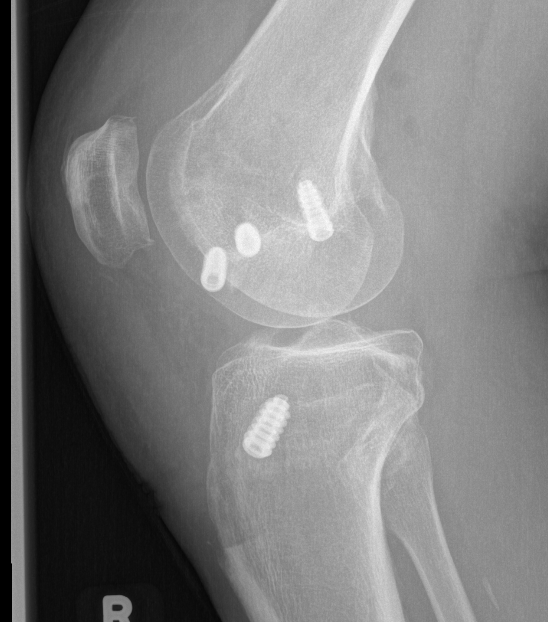

ACL + LaPrade reconstruction of LCL and popliteus